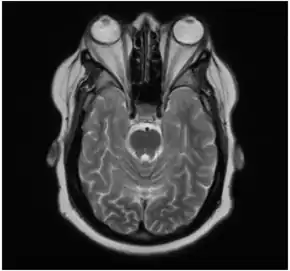

Bilateral exophthalmos as seen on MRI.

In the case of Graves' disease, the displacement of the eye results from abnormal connective tissue deposition in the orbit and extraocular muscles, which can be visualized by CT or MRI.[1]